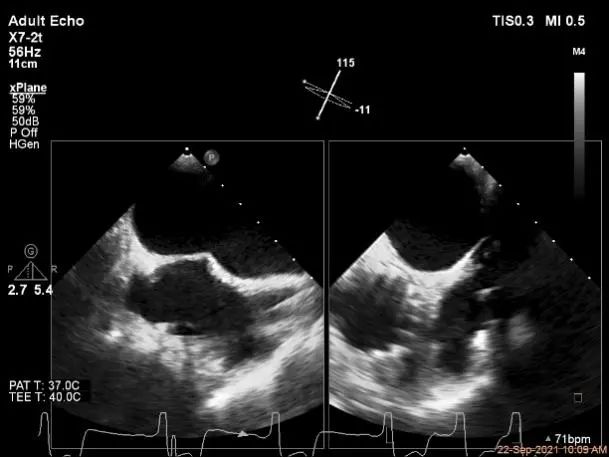

术中超声

P2区脱垂,宽14.8mm,Gap:3.3mm

3D-color,返流重度,3+级

麻醉状态下左肺静脉血流频谱

MVA:6.67cm²

房间隔穿刺点选择

穿刺高度:4.3cm

瓣叶捕获后,前叶抓捕长度9.1mm,后叶抓捕长度7.8mm

外侧残余少量分流

第一个夹子外侧残余小脱垂

残余分流主要来源于残余脱垂区域

评估瓣口条件,平均跨瓣压差:2mmHg,决定在第一个夹子外侧下第二个夹子